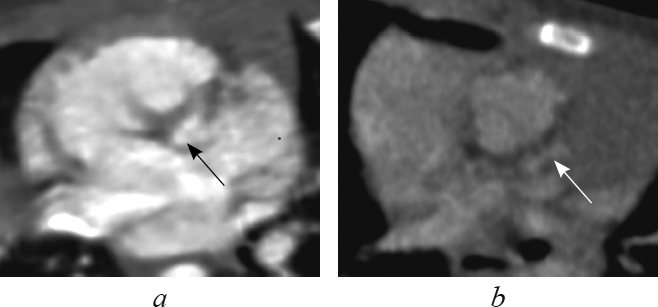

В данной статье приведены результаты анализа данных рентгеновской компьютерной томографии с внутривенным болюсным введением контрастного вещества детей с транспозицией и корригированной транспозицией магистральных артерий путем последовательного построения многоплоскостных реформаций, ориентированных на оси сердца. Из 148 детей со сложными врожденными пороками сердца и магистральных артерий транспозиция магистральных сосудов встречалась у 13 пациентов (в возрасте от 1 до 144 дней жизни; 9 — мужского пола, 4 — женского пола), корригированная транспозиция магистральных сосудов — у 4 пациентов (в возрасте от 6 мес. до 15 лет 6 мес.; 2 — мужского пола, 2 — женского пола). В статье подробно описаны анатомические характеристики, на основе которых определяется морфология каждой камеры сердца, и реформации, в которых они оцениваются. В статье приводится сравнительная характеристика структур сердца и магистральных артерий при транспозиции и корригированной транспозиции магистральных артерий в каждой отдельно взятой реформации, ориентированной на оси сердца. По результатам анализа последовательно построенных реформаций, ориентированных на оси сердца, указаны и проиллюстрированы характерные анатомические признаки транспозиции и корригированной транспозиции магистральных сосудов. Установлено, что из перечня предлагаемых реформаций, ориентированных на оси сердца, характерные анатомические признаки транспозиций достоверно определяются в следующих реформациях: по длинной оси приносящего тракта правого желудочка; левых камер сердца; приточных отделов желудочков; по короткой оси на уровне магистральных сосудов. Многоплоскостные реформации, ориентированные на оси сердца, на основе данных КТ-ангиокардиографии позволяют дать полную и точную анатомическую оценку сердца и магистральных сосудов, что важно при планировании оперативного вмешательства при врожденных пороках сердца.